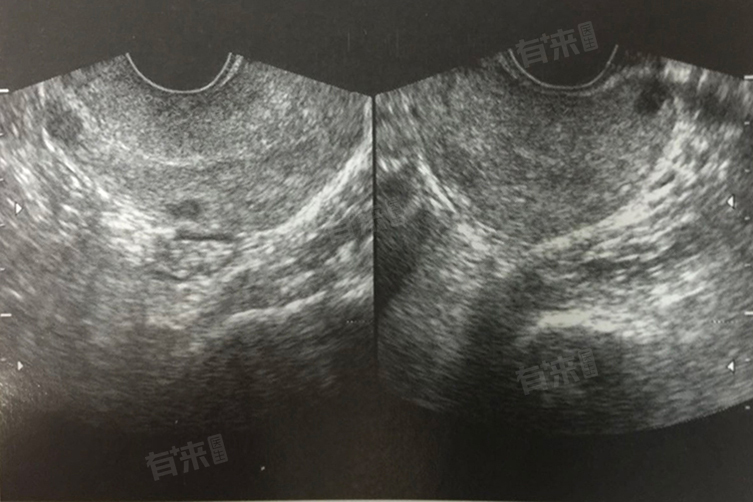

癥瘕病是中医的一种病症名称,是对女性腹部肿块类疾病的统称,在现代医学中涵盖了多种疾病,如子宫肌瘤、卵巢囊肿、盆腔包块等。

- 癥瘕病的主要症状是腹部可触及肿块,根据肿块的性质、大小、部位以及患者体质的不同,症状也有所差异。有的患者可能会出现月经紊乱,如月经量增多、经期延长、闭经等。

有的会伴有腹痛,疼痛程度不一,可为隐痛、胀痛或刺痛;还可能出现带下异常,量多、色黄、质稠等;部分患者可能会出现不孕,因为癥瘕影响了胞宫的正常功能,阻碍了受孕。